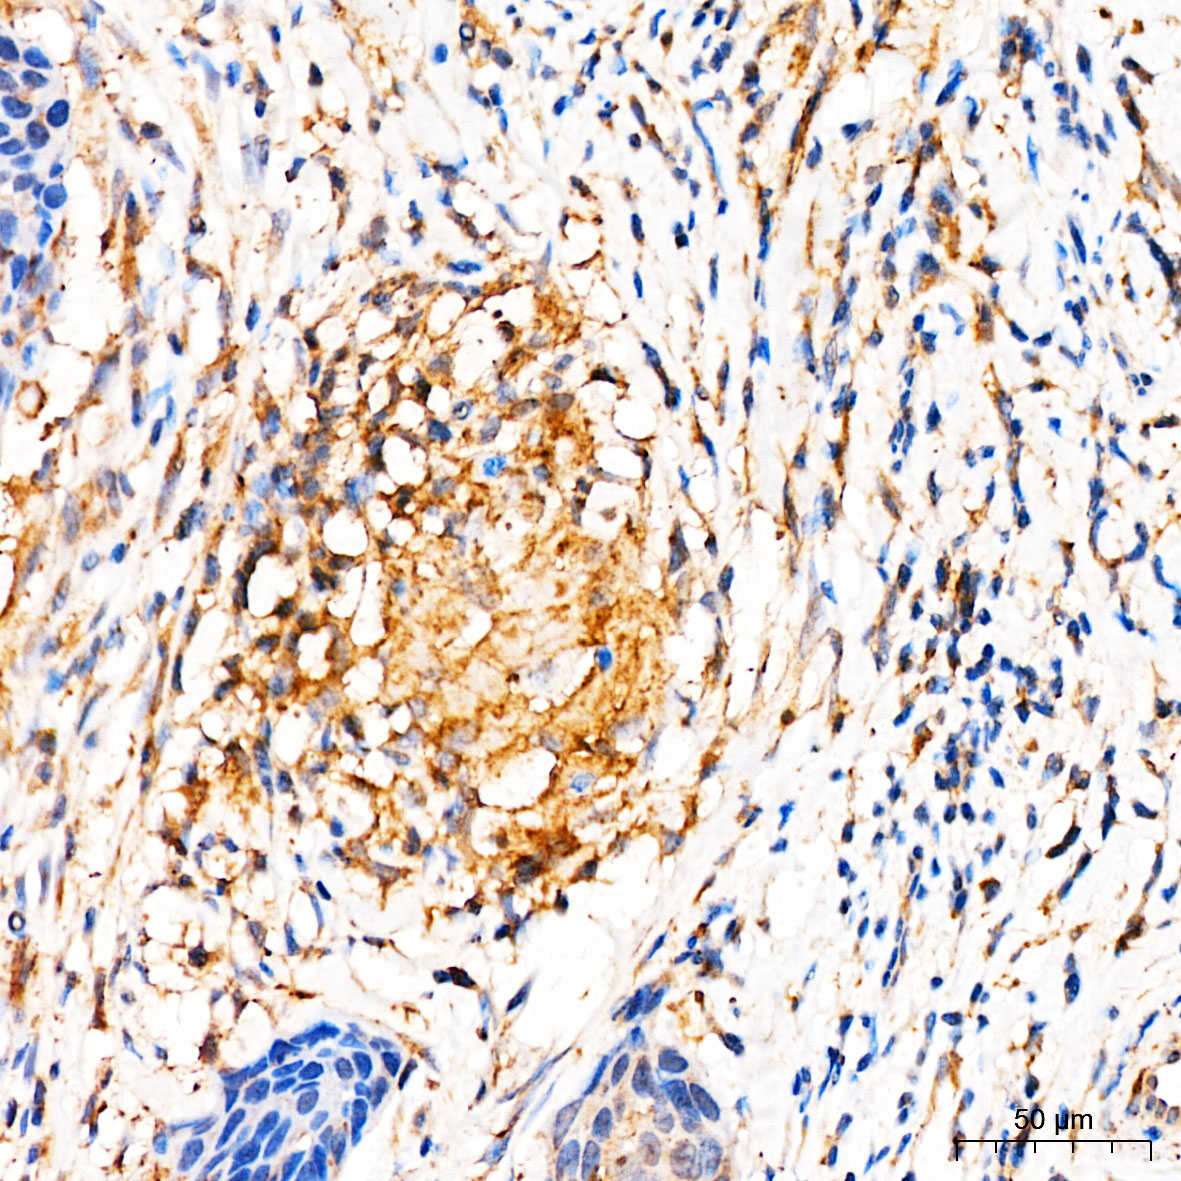

| Immunohistochemistry analysis of paraffin-embedded Human cervical squamous cell carcinoma tissue using [KD Validated] MRPL27 Rabbit pAb (A25221) at a dilution of 1:100 (40x lens). High pressure antigen retrieval was performed with 0.01 M citrate buffer (pH 6.0) prior to IHC staining. |